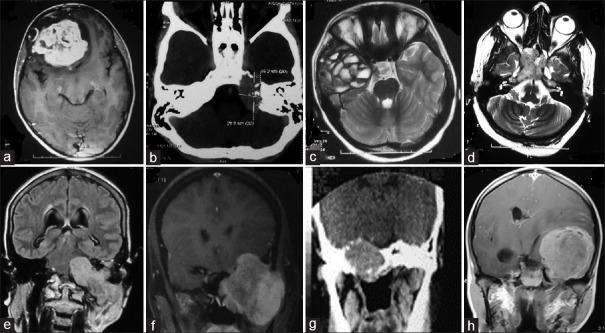

颅底骨病变:管理细节;来自三级护理中心的回顾性分析

We have surgically managed 41 cases of skull base bony tumors. It includes 11 patients of anterior skull base, 13 middle skull base, and 17 posterior skull base bony tumors. The most common bony tumor was chordoma 15 (36.6%), followed by fibrous dysplasia 5 (12.2%), chondrosarcoma (12.2%), and ewings sarcoma-peripheral primitive neuroectodermal tumor (EWS-pPNET) five cases (12.2%) each. There were more malignant lesions ( = 29, 70.7%) at skull base than benign ( = 12, 29.3%) lesions. The surgical approach employed depended on location of tumor and pathology. Total mortality was 8 (20%) of whom 5 patients were of histological proven EWS-pPNET.

我们手术治疗了41例颅底骨肿瘤。其中包括11例前颅底、13例中颅底和17例后颅底骨肿瘤。最常见的骨肿瘤是脊索瘤15例(36.6%),其次是骨纤维发育不良5例(12.2%)、软骨肉瘤(12.2%)以及尤因肉瘤-外周原始神经外胚层肿瘤(EWS-pPNET)各5例(12.2%)。颅底的恶性病变(n = 29,70.7%)比良性病变(n = 12,29.3%)更多。所采用的手术入路取决于肿瘤的位置和病理类型。总死亡率为8例(20%),其中5例经组织学证实为EWS-pPNET。